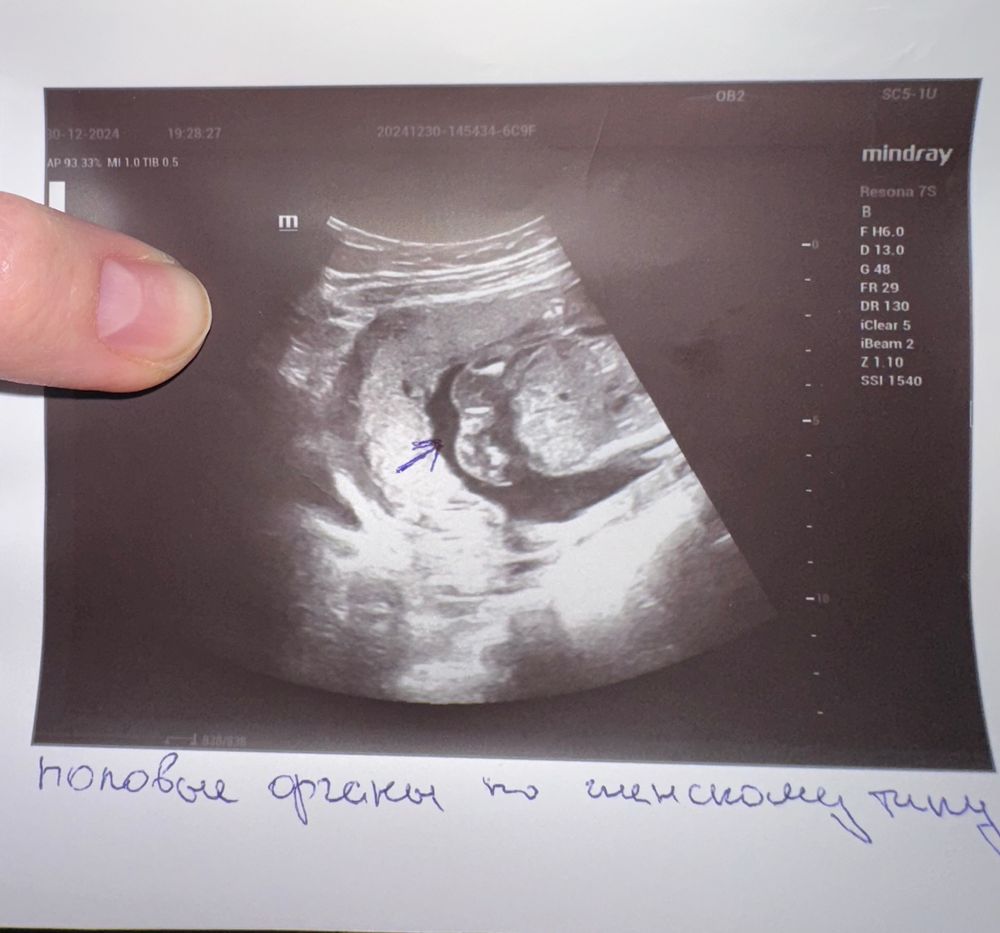

Пол малыша30.12 узнали пол ровно в 18 недель, но врач сказал на 85% уверен 🤨 Дали фото нашей🍑😅 Кто что скажет похоже же на девочку? 😁

Девичий пирожок.

У парней уже все хорошо видно на этом сроке